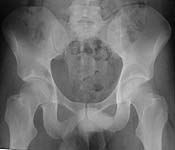

From: Nachshon Shazar

I would like to present an acetabular fx in which the AP view showed even less displacement, but Judet view proved it to be a 6 mm displaced posterior column acetabular fx. (X ray attached) I believe that the case we are discussing is a displaced posterior column fx (iliac view is needed) and ORIF is probably indicated.

AP Pelvis

Iliac View

CT

Nachshon Shazar, Tel Aviv, Israel